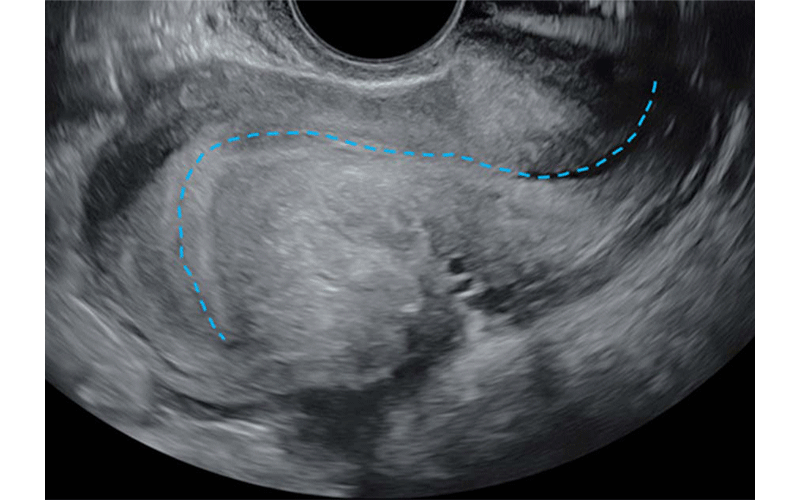

Transvaginal US in a 41-year-old patient with chronic pelvic pain and dyschezia shows the “question mark sign” uterine configuration. Longitudinal view shows an abnormal uterine configuration in which the uterus is sharply retroflexed because of deep endometriosis that is tethering the posterior cervix to the uterine corpus. This observation is usually identified by abnormal endometrial axis with sharp retroflection of the uterine fundus (dashed blue line) and constitutes a category B (ie, indirect endometriosis) observation.